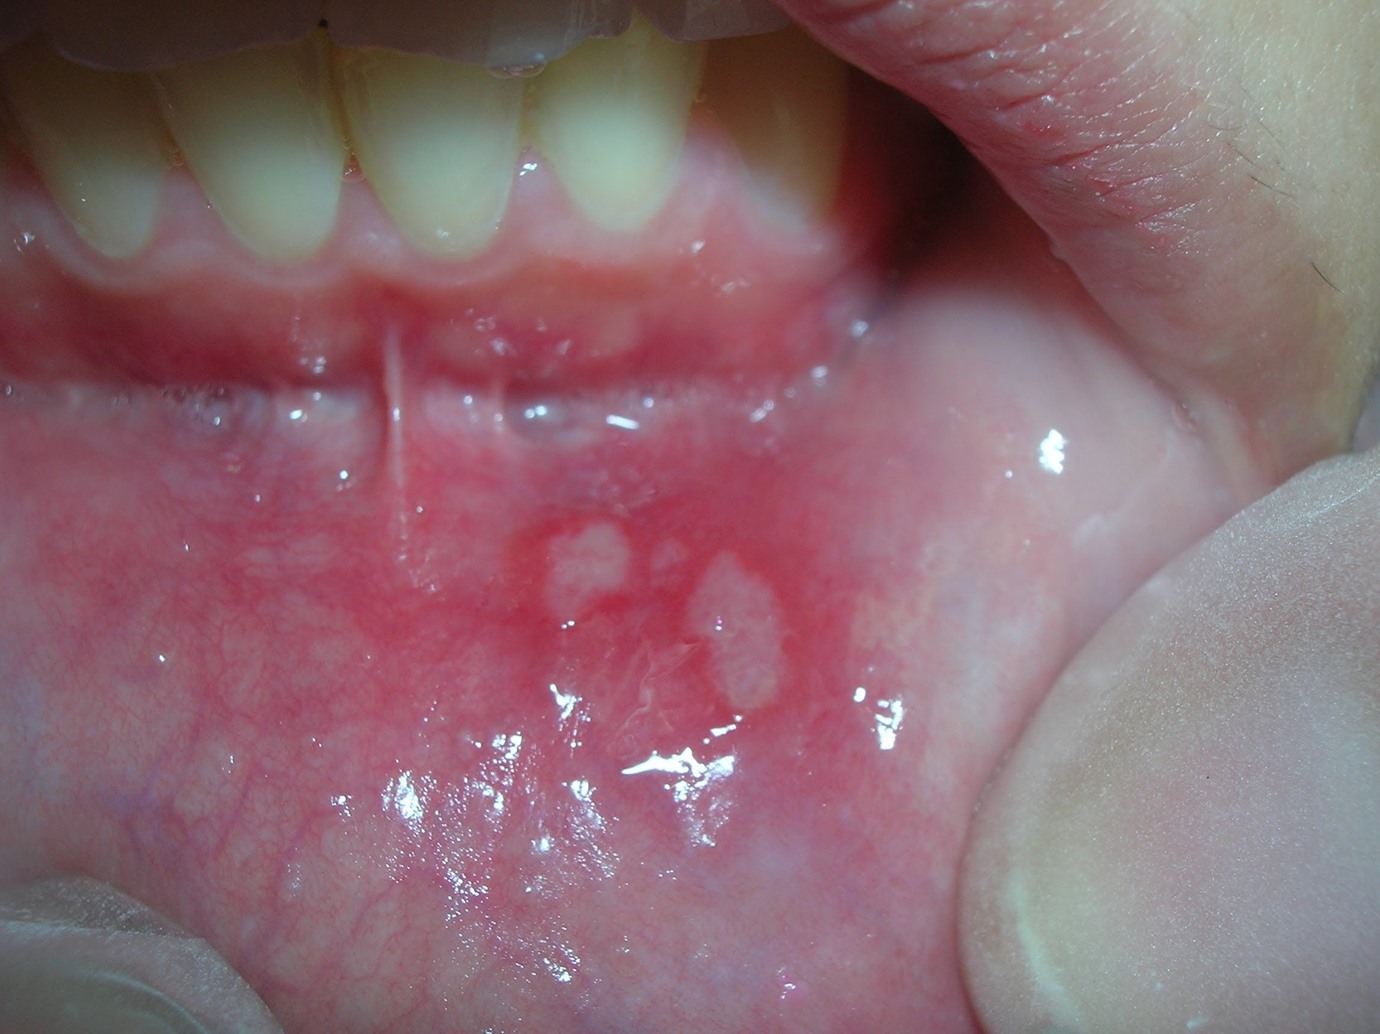

أكدت دراسة جديدة أجراها باحثون من الأكاديمية الصينية للعلوم الطبية أن بكتيريا الفم تزيد خطر الإصابة باضطرابات الأمعاء.

وحدد الباحثون بعض الأنواع من البكتيريا الفموية التي ترتبط ببكتيريا الأمعاء وبينها الكلبسيلا الرئوية وهي سلالة شائعة في الفم البشري ووجد أن لها علاقة باضطرابات الأمعاء خاصة التهاب القولون.

وأشارت الدراسة إلى أن هذه البكتيريا مقاومة للمضادات الحيوية وتتحفز لتستعمر القناة الهضمية، مضيفة أن تجويف الفم قد يكون مركزا لتلك البكتيريا التي تسبب اضطرابات الأمعاء.